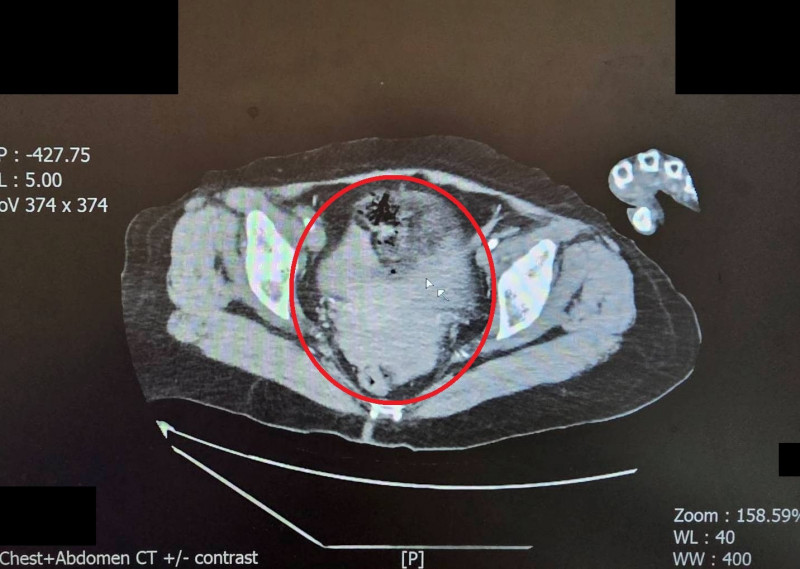

大千醫院指出,陳女被送抵急診時,出現嚴重的雙側氣胸與皮下氣腫,呼吸極度困難。經全身電腦斷層掃描發現,強大的撞擊力導致她的左側橫隔膜破裂,原本應在腹腔的胃部及部分腸道,竟位移進入左側胸腔,嚴重壓迫左肺,導致肺部無法擴張。此外,檢查更發現其下腹部大量出血(腸繫膜血管破裂)、左腳踝骨折,背部還有大面積的2至3度擦燙傷,傷勢遍布全身。

外科醫師馮啟彥評估後,決定採取難度較高的腹腔鏡微創手術。馮啟彥說:「透過腹腔鏡的3個小傷口,先往左上腹腔將移位的胃腸道拉回原位,並修補破裂的橫隔膜;接著隨即將鏡頭倒轉往骨盆腔,修補兩處大量出血的腸繫膜血管。」這種方式不僅避開了大面積傷口,也大幅減少病人的體力消耗。